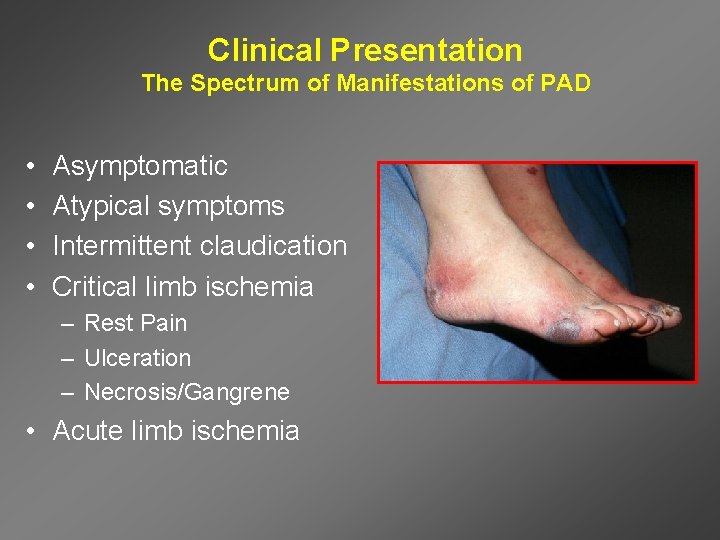

Clinical Presentation The Spectrum of Manifestations of PAD • • Asymptomatic Atypical symptoms Intermittent claudication Critical limb ischemia – Rest Pain – Ulceration – Necrosis/Gangrene • Acute limb ischemia